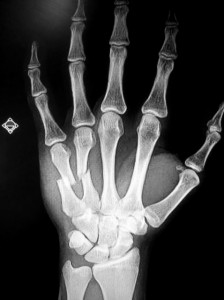

Metacarpal fractures are common hand injuries. They can occur from a variety of injuries such as a fall, a motor vehicle collision, or punching a wall. There are five metacarpals — one for each finger and the thumb. The metacarpals contribute to the bony architecture of the hand. Satisfactory healing of this fracture is important to restoring overall hand function. A fracture of the metacarpal neck of the small finger is sometimes called a “boxer’s fracture” as they can be seen in punching injuries. “Fracture” is simply the medical term for “broken bone.” The image below demonstrates a shaft fracture of the 5th metacarpal bone.